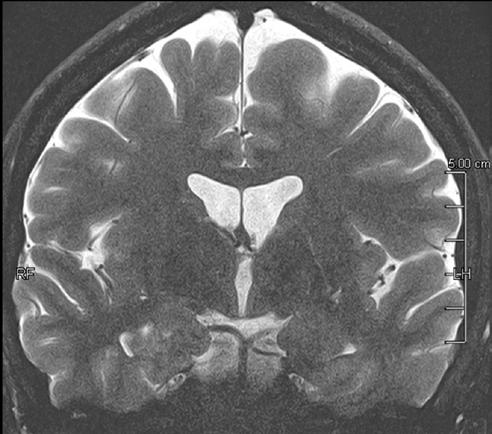

Fig 1: Next generation MRI is being used to gather data on brain tissue volumes Dr. Steve McNally

From this season at Manchester United Football Club, we have started to gather data by using MRI (see fig 1) to measure volumes of brain tissue in specific areas, to monitor for a decrease in volumes over time. If the volumes become unusual or deviate from the norms that we would expect, it may help us identify early changes of CTE that need closer monitoring. This is a new, long-term data gathering study in our cohort of players that has been facilitated with the new next generation MRI3 now in place at our medical centre.